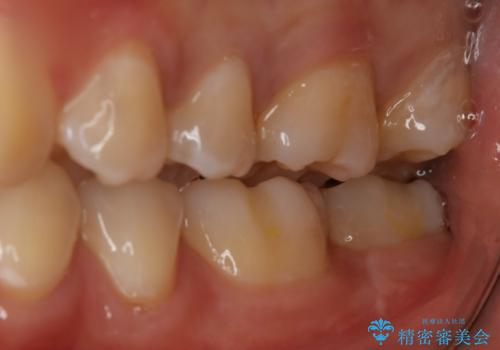

奥歯を治療したい フルジルコニアクラウン

- 99000円(フルジルコニアクラウン+仮歯)費用は治療当時の料金となります